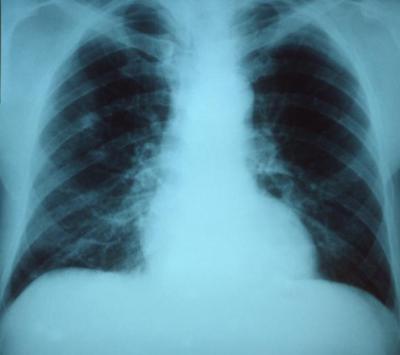

Researchers report they have found a way to disrupt the spread of antibiotic-resistance genes among S. pneumoniae bacteria, which can contribute to pneumonia (pictured), meningitis and other dangerous ailments.

(Photo Credit: US Centers for Disease Control and Prevention)